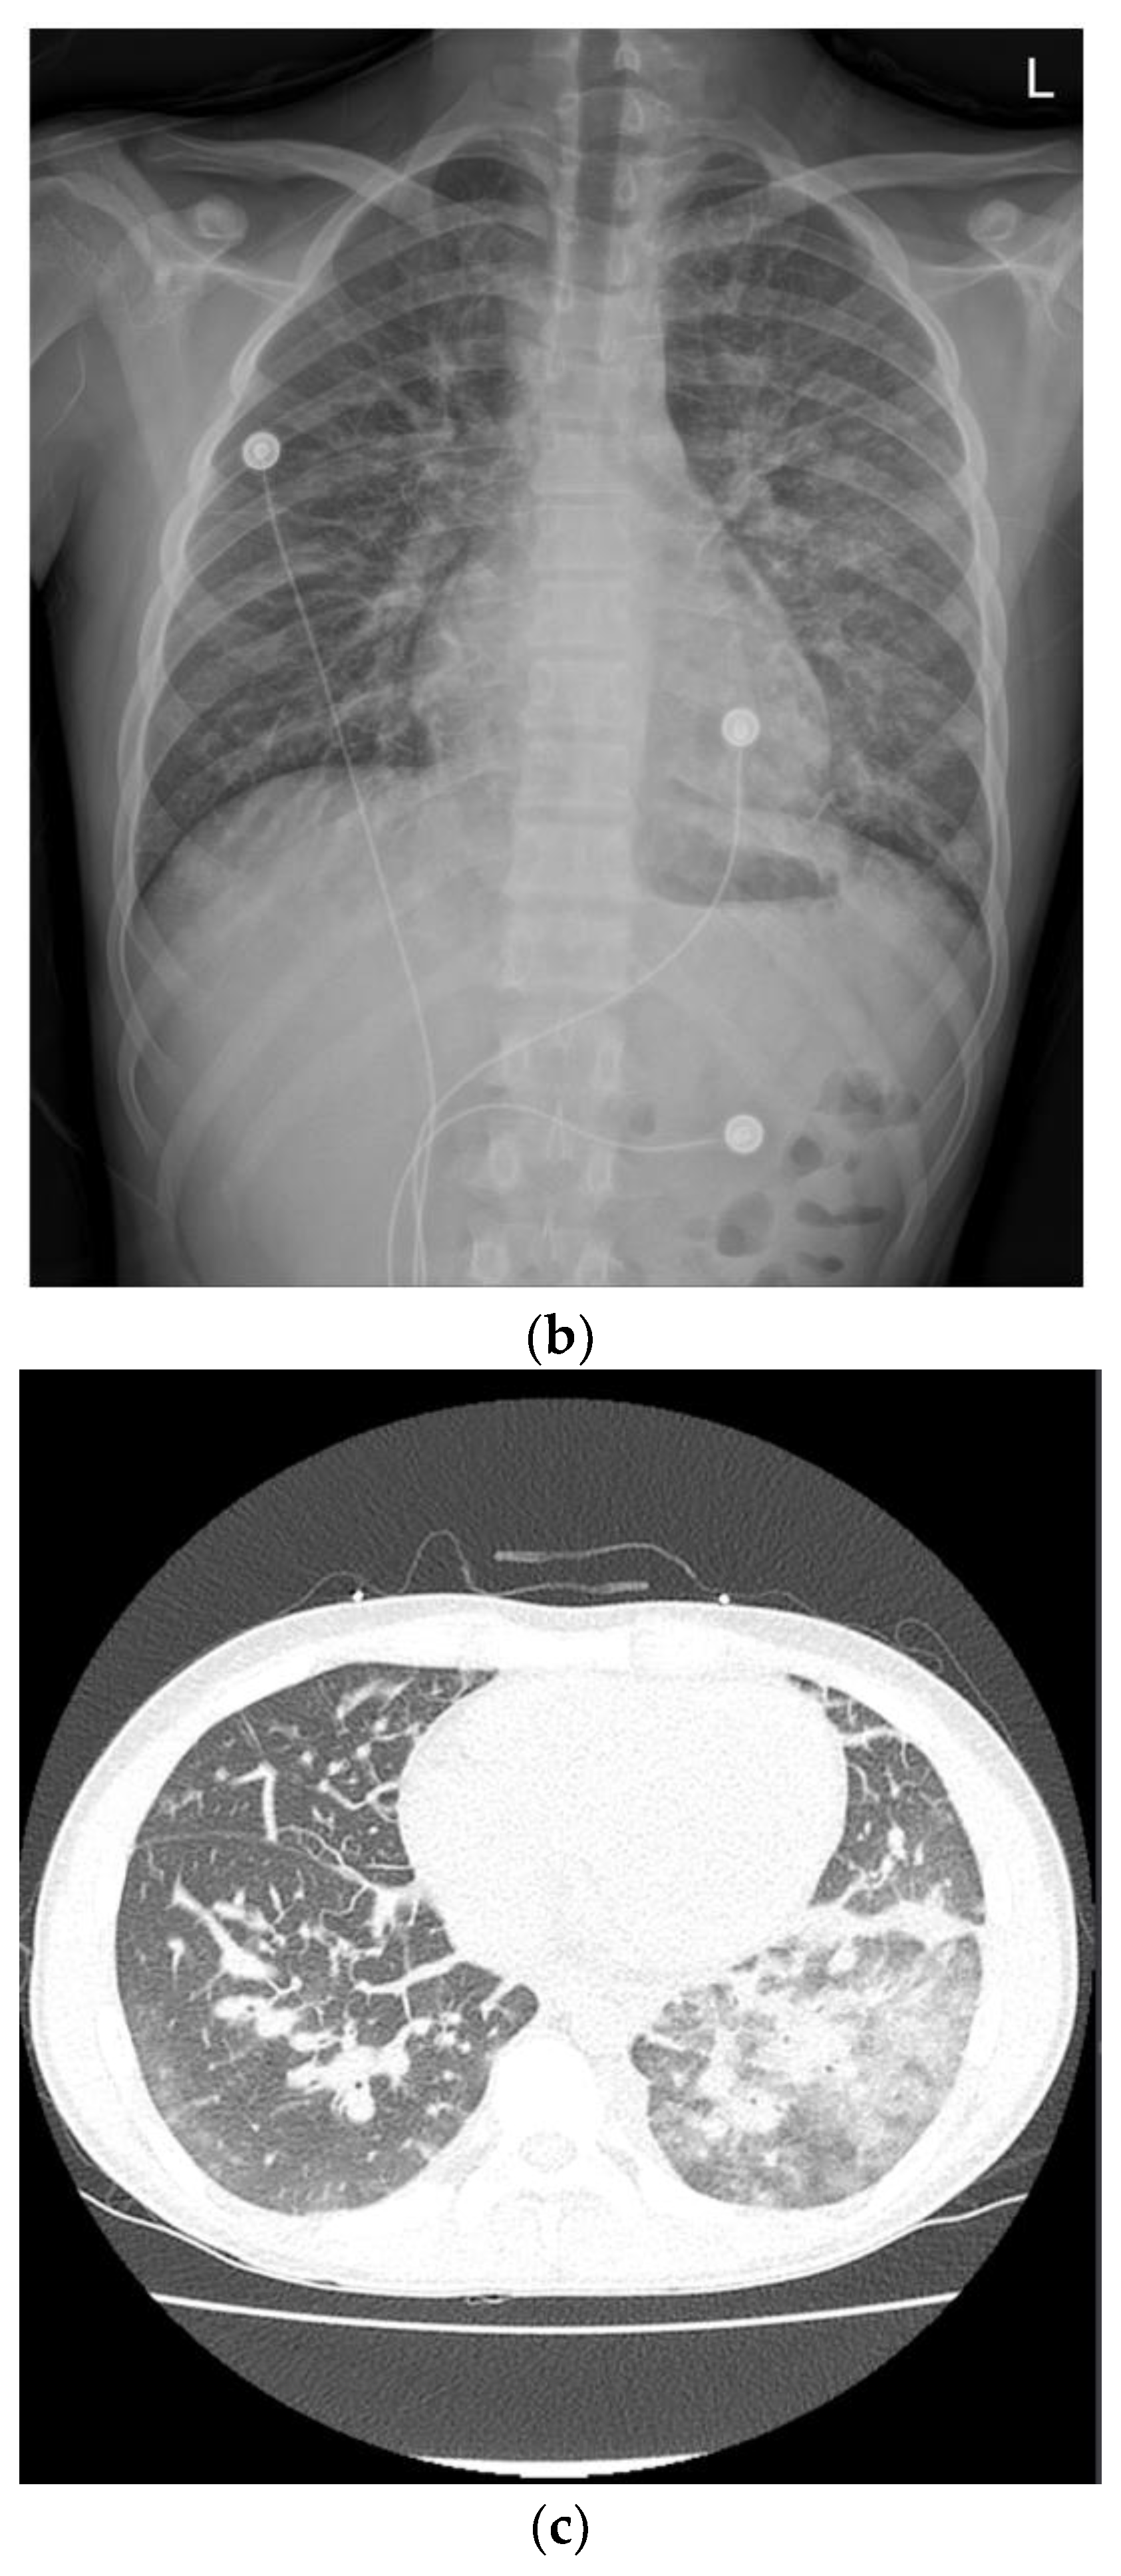

Intermittent episodes of bloody stools continued, and symptoms and vital signs were controlled through supportive care, including intravenous hydration and blood transfusion. CD was suspected, so he was treated with exclusive enteral nutrition with a steroid to control the myocarditis. On the 13th day of admission, the patient had no symptoms other than intermittent bloody stools. All cardiac markers were normal, and sST2 was also reduced to 98 ng/mL. Therefore, the patient was transferred to the general ward for diagnosis and treatment of IBD. MR enterography revealed terminal ileitis without stricture. Gastroduodenocolonoscopy revealed improvement in the ileocecal valve and terminal ileal ulceration with no other lesions (Figure 4).

Figure 4.

Magnetic resonance enterography demonstrated wall thickening of the distal ileum, including the ileocecal valve (a). Colonoscopy revealed healing scars and pseudopolyps of the terminal ileum (b).

Capsule endoscopy was performed to evaluate mucosal lesions in the small intestine. Three or more ulcerations were confirmed, and fresh blood due to active bleeding was observed in the distal small intestine (Figure 5).

Figure 5.

Capsule endoscopy revealed three or more ulcers of various sizes (a) and active bleeding in the distal ileum (b).